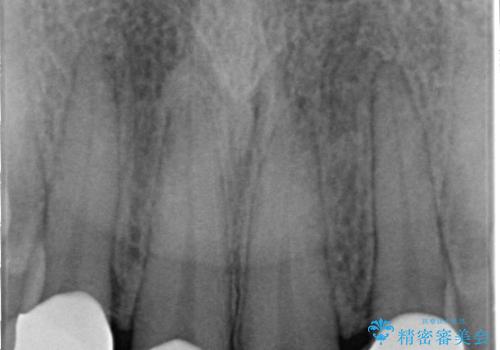

前歯の形気になる セラミッククラウン(SP)

- 矯正終了した患者様で、前歯の形が気になるということで

セラミッククラウンにて治療された方の症例です。

また、神経がある歯なのでシミたりすることが場合によってはありますので、担当歯科医師にご相談ください。